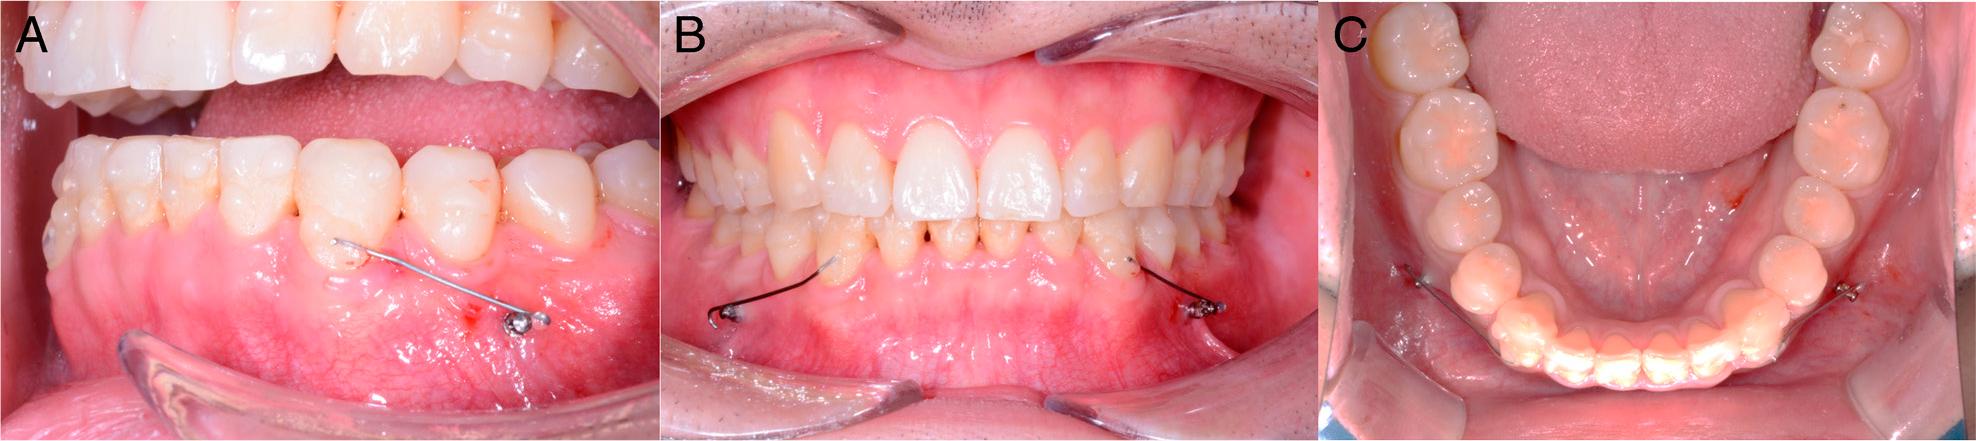

After 18 months, treatment was completed. A lingual fixed retainer was bonded between the mandibular canines. A removable circumferential retainer was also provided for the patient.

The patient’s facial profile remained straight (Figure 9). The molar relationships were maintained, and the occlusion showed acceptable interdigitation. The maxillary and mandibular arches had been changed to ovoid. The anterior crowding was resolved. Furthermore, the rotation and angulation of the right mandibular canine improved (Figure 10).

Post-treatment records, including extraoral and intraoral photographs.

Model superimposition. The yellow colour denotes the pre-treatment model, and the orange colour represents the post-treatment model. The registrations were performed on the occlusal surfaces of the first and second molars. A, Maxillary dentition. B, Mandibular dentition. C, Oblique view.

The panoramic radiograph showed the distal movement of the right mandibular canine root (Figure 11). The post-treatment cephalometric measurements and superimposition of the pre- and the post-treatment films demonstrated that incisal proclination occurred without compromising the facial profile (Figure 11, Table I).